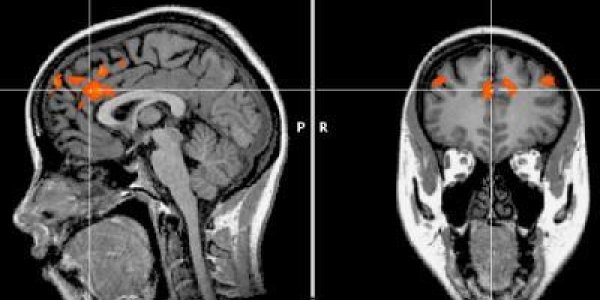

The anterior insular cortex is a small region of the brain, but it plays a big role in human self-awareness and in neuropsychiatric disorders. A unique cell type, the von Economo neuron (VEN), is…